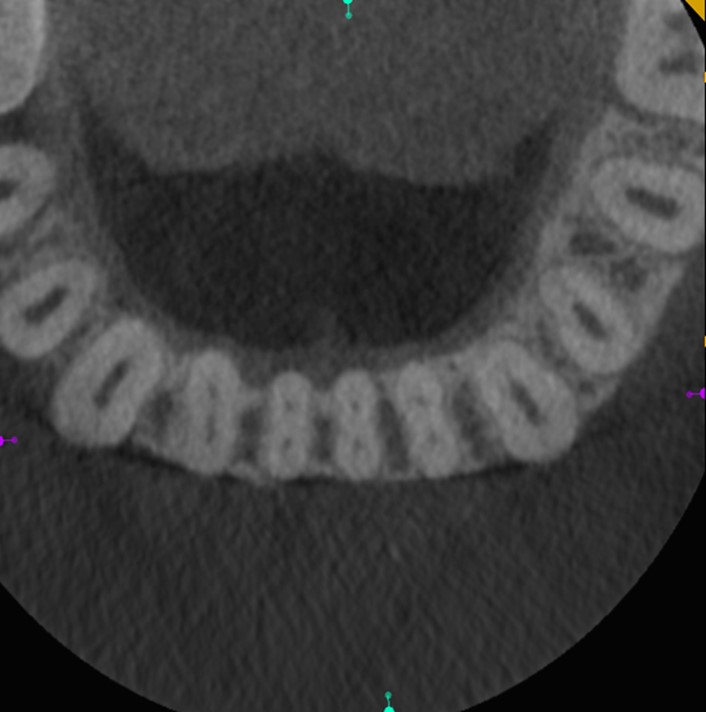

Surveying pulpal anatomy before initiating treatment is another area in which CBCT can benefit a trained operator. Understanding the internal anatomy of the root canal system can help in treatment planning a nonsurgical case, as well as a microsurgical case, to avoid procedural mishaps. CBCT can also facilitate the conservation of tooth and root structure.For instance, knowing whether a maxillary molar has a second mesiobuccal (MB) canal can help the practitioner avoid troughing or removing precious dentin when there is no MB2 canal. In addition, more accurately locating the MB2 canal when it is visible on CBCT also assists in conserving tooth structure. The same holds true for a possible lingual canal or additional canal(s) in a mandibular incisor (Figure 9) or bicuspid.

Fig 9. 3D CBCT image of mandibular incisors with two canals.

Figure 9